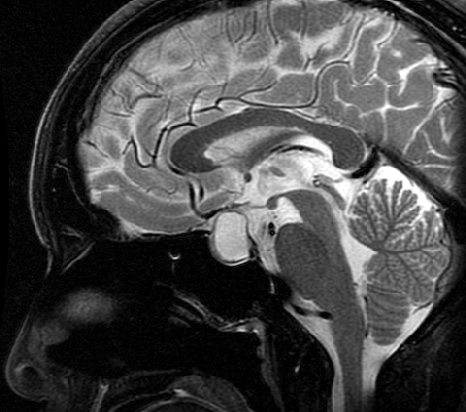

下垂体は鼻の付け根の奥のトルコ鞍という頭蓋骨の小さなポケット(大きさ1cm大)のようなところにあります。

トルコ鞍の中で成長し、大きくなるとトルコ鞍から頭蓋内へ突出し(鞍上部へ突出し)、脳神経を圧迫します。腫瘍が鞍上部へ突出し視神経を強く圧迫すると、視機能の低下(視野欠損、視力低下)を招きます。視野欠損は両耳側半盲といって、両目の外側(左右の目の耳側)の視力が欠けてしまいます。この状態になると、人混みでぶつかり易くなったり、車の運転で衝突事故を起こしやすくなります。

トルコ鞍内から鞍上部にかけて発生しますが、鞍上部に発生することが一般的です。